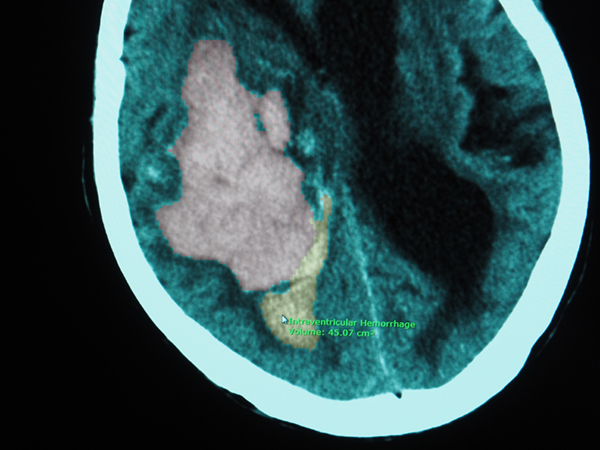

デモは,AIのインテグレーションについて,グローバル向けに展開しているRIS(ワークリスト)とPACSのワークフローで説明を行った。検査が終了しワークリスト上に読影のタスク(検査リスト)が表示されている状態で,放射線科医がこれから読影を行うというシチュエーションで説明された。ワークリストに表示された段階で,すでにAIによる事前チェックが終了し,所見と確信度が表示されている。さらに,所見内容から推定される緊急度を判断して優先度の高い順に並べ替えられて表示されている。患者を選択し画像を立ち上げると,画面内にAI(REiLI)のアイコンがあり,クリックすることで画像上にAIで自動検出された病変や構造がオーバーレイ表示されるようになっている。さらに,自動検出された結果はテキストとしてレポートに送ることができる。これはAPI(Application Programming Interface)として用意され,他社のレポートシステムでも,またティーチングファイルとしても利用可能になっている。

AIのアイコンをクリックすることで病変のあると思われるスライスを示す。

その部位をクリックすると病変を認識した上で表示

症例名や病変の大きさをAIが自動認識

このように,富士フイルムグループのAI環境のコンセプトは,データの入力から解析結果の出力までオープンな環境で構築されているのが特徴である。さらに,読影システムへの実装では,従来の環境はそのままに,AI利用のために新たな操作方法などをおぼえることなく使えるシステムをめざしているのも特徴だ。現状でデモに搭載されているアルゴリズムは,自社開発の脳卒中(脳内出血,くも膜下出血,脳梗塞)や肺がんなどの7つと,Lunit(胸部X線画像から4つの疾患を検出するアルゴリズム)Riverain Technologies,Koios Medicalのサードパーティ製,UCLAで開発されたカテーテルの自動検出アルゴリズムで,自社だけでなくさまざまなアルゴリズムが一つのプラットフォームに統合されている。